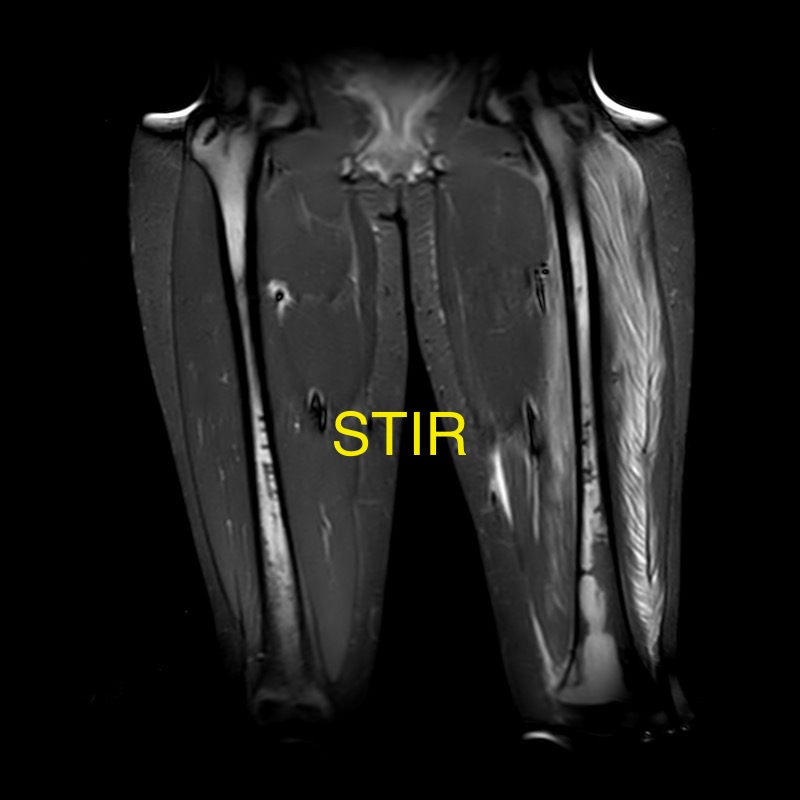

14 year old bone marrow

Dear OCADers, Happy Friday. I would like to get your opinion on this 14 year old female who presented with left lower extremity pain. Pancytopenia was incidentally noted on her work up. She had myositic changes and a fluid collection in her left anterior muscle compartment. I am sharing 4 coronal images of her femora […]